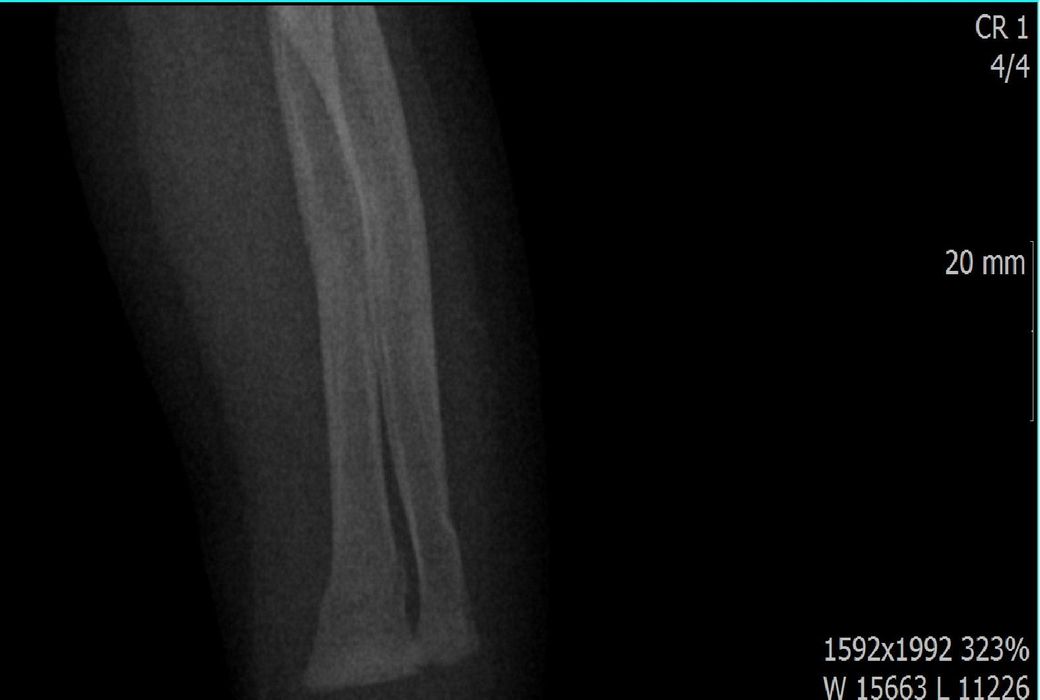

x ray 팔 골절 시기 추정해보고 싶습니다.

다름이 아니라, 첨부드린 엑스레이(X-ray) 사진처럼 골절 사실을 알게 되고 골절 발생 시점 대략적으로나마 추정시기를 파악하려고 문의 드리게 되었습니다

1) 3월 30일 촬영한 X-ray만으로 정확한 골절 시기를 100% 특정하는 데에는 한계가 있다는 점 충분히 인지하고 있기에 촬영날짜 기준으로 대략적으로 어느정도 시점에서 발생되었을 것으로 추측(ex 당일, 7~10일전, 7~14일 전, 10일 ~ 20일전, 14일 ~ 30일전 등등등)되는지 이해하고 싶습니다.

• 1번 째 사진